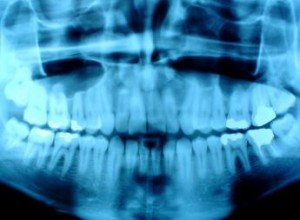

X-rays: A Necessity For Your Oral Health [VIDEO]

X-rays are essential to a person’s oral health, and at Grandview Corners Dental and Wellness Centre in Surrey, we want to ensure that people are getting regular X-rays for their teeth. So what is the big deal about getting X-rays? X-ray exams reveal the state of...